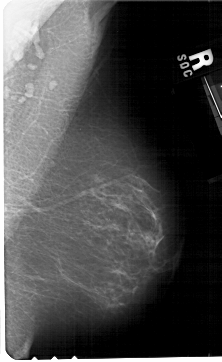

A_1479_1.RIGHT_MLO

RIGHT_MLO LINES 5416 PIXELS_PER_LINE 3316 BITS_PER_PIXEL 12 RESOLUTION 43.5 NON_OVERLAY